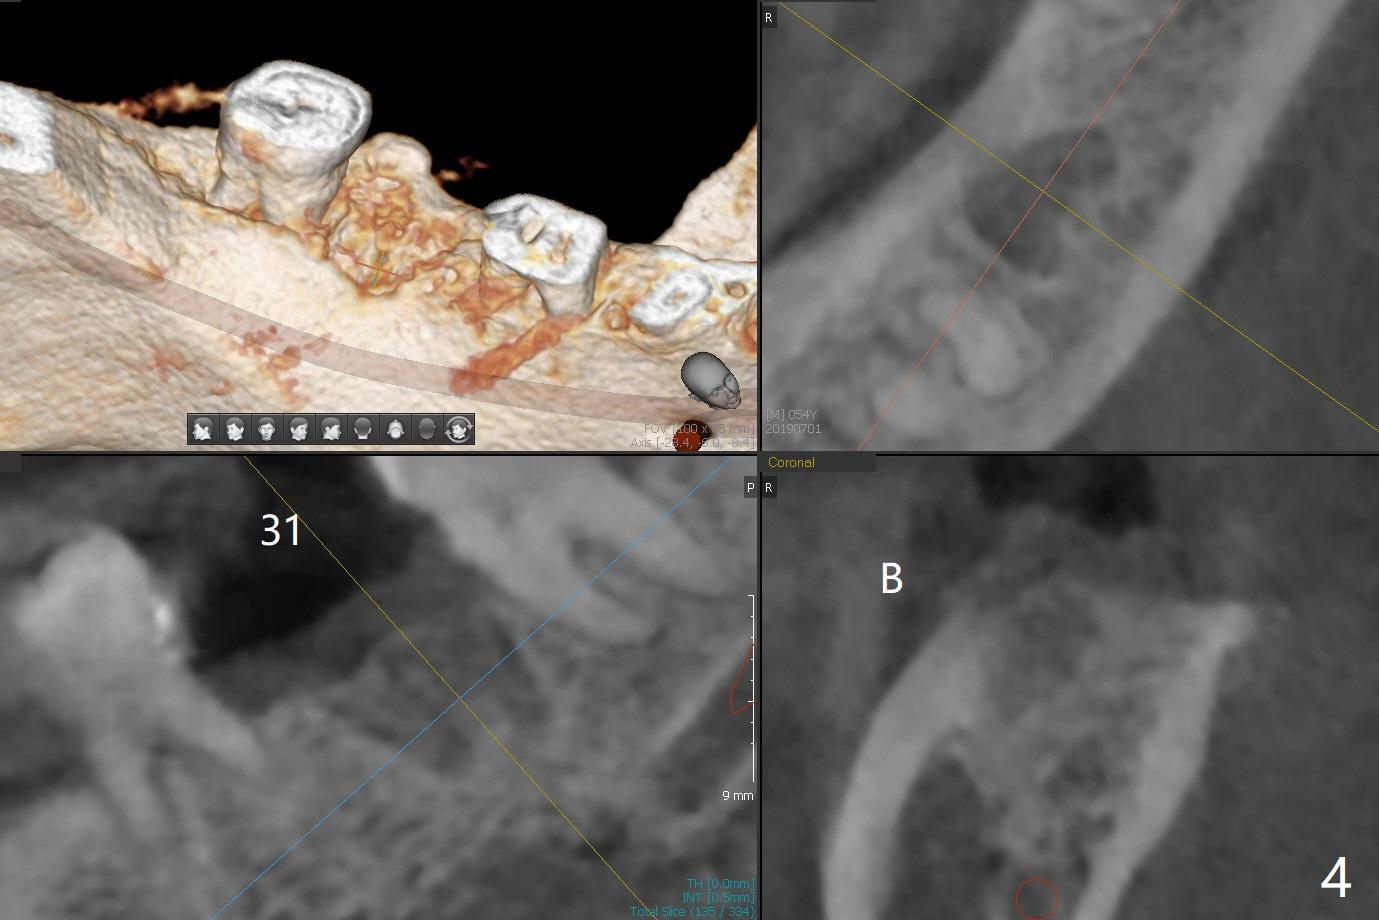

Bone Density Post Extraction with or without Bone Graft

Edentulous Lower Molar